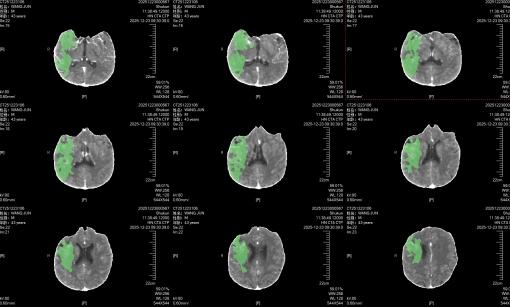

40岁的张先生(化名)正值壮年,平时身体硬朗,无基础病史。然而就在几个小时前,他突然左侧肢体完全无力,连抬手的力气都没有,说话含糊不清,意识也逐渐模糊。家人紧急将他送往我院神经内科。CT检查结果显示:右侧颈内动脉+大脑中动脉闭塞,右脑半球广泛低灌注。 “如果不及时开通血管,患者将面临终身瘫痪的风险。”接诊医师神色凝重地说。

经过进一步DSA检查,病因终于浮出水面——右侧颈内动脉夹层。

时间就是生命,每一分钟的延误都意味着患者离危险又近了一步。神经内科手术团队立刻到位,为患者制定了“先通血管、再修血管”的方案。当 DSA 显示血流恢复如初时,手术室内所有人都松了一口气,这个年轻的家庭,终于不用面对终身残疾的打击了。